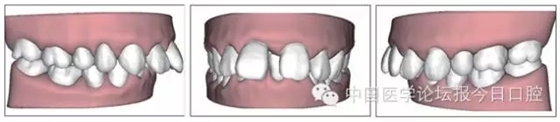

本病例為慢性牙周炎致前牙漂移、深覆(牙合)患者。本病例采用無托槽隱形矯治技術(shù)進行治療。無托槽隱形矯治器具有可摘戴、便于口腔衛(wèi)生維護和牙周治療的優(yōu)點,更適合于伴有牙周炎的錯(牙合)畸形患者的治療。 患者男,48歲,前牙有縫、前突求診。 患者面部對稱,側(cè)面觀上頜前突,下頜后縮。 口內(nèi)情況:恒牙列,24、34、44缺失,磨牙Ⅲ類關(guān)系,上牙列散隙,上前牙扇形漂移。前牙深覆(牙合)、深覆蓋??谇恍l(wèi)生較差,11與12間牙齦乳頭紅腫,多個牙探診有牙周袋形成,11松動Ⅰ度,余切牙松動(-),患者面像及口內(nèi)像如圖1、2所示。 圖1 治療前面像 圖2 治療前口內(nèi)像 全口曲面體層片(圖3)顯示,患者全牙列牙槽骨吸收;根尖片(圖4)示11近中牙槽骨角形吸收已達根尖1/3,21牙槽骨嵴頂吸收至根1/2,23牙槽骨近中骨板角形吸收至根1/2。磨牙區(qū)骨嵴頂吸收3mm。治療前頭顱側(cè)位片見圖3,治療前ODS模型見圖5。 圖4 治療前根尖片 圖5 治療前ODS模型 牙型:安氏Ⅲ類。骨型:Ⅱ類。面型:上頜前突,下頜后縮。 問題列表為:①上牙列間隙;②上切牙病理性牙移位;③前牙深覆(牙合)、深覆蓋;④24、34、44缺失;⑤慢性牙周炎。 矯治目標包括:①排齊牙列,關(guān)閉牙列間隙;②改善前牙深覆(牙合)、深覆蓋;③改善牙周狀況。 矯治設(shè)計有:①牙周基礎(chǔ)治療與維護。②壓低、內(nèi)收上切牙,關(guān)閉上牙列間隙。③壓低下切牙,伸長下后牙,整平Spee曲線,改善前牙覆(牙合)、覆蓋。 患者進行全口齦上潔治、齦下刮治,口腔衛(wèi)生宣教,并按牙周醫(yī)師的要求,每2~3個月行牙周檢查與治療。 牙周基礎(chǔ)治療結(jié)束3個月,開始隱形矯治。于14、25、35、36、45、46上粘接附件(圖6),于16、26(牙合)面粘接(牙合)墊。 圖6 ODS設(shè)計附件粘接圖示 矯治過程中注意(牙合)墊是否脫落或磨損,及時修補。 注意上前牙內(nèi)收時有無咬合干擾,及時調(diào)(牙合)。下頜前磨牙伸長到位后,磨除16、26(牙合)墊。 下頜佩戴第24步矯治器時,分別在36、37、46、47的頰、舌側(cè)粘接舌扣,矯治器上預(yù)留伸長空間,用3/16英寸、3.5盎司皮圈牽引,輔助伸長下磨牙(圖7)。 患者共戴用矯治器上頜32步,下頜26步。 矯治后,牙列間隙關(guān)閉,面型及覆(牙合)覆蓋改善。11根尖片(圖8)顯示,治療后較治療前,牙周支持組織增加,牙槽骨角形吸收區(qū)水平向縮小0.3mm,垂直向縮小0.6mm。11松動Ⅰ度,余切牙無松動。 圖8 治療后根尖片 圖9 治療后口內(nèi)像 圖10 治療后X線檢查 圖11 治療后ODS模型 正畸-牙周聯(lián)合治療對于牙周組織的影響 多學(xué)科綜合治療牙周炎患者不再是正畸治療的禁忌證。良好的牙周治療為正畸治療中的牙齒移動打下堅實基礎(chǔ),而正畸治療排齊牙齒、去除(牙合)干擾,有利于牙周健康。 牙周炎患者的正畸治療必須在牙周炎癥得到控制后才能進行,否則,菌斑會隨著牙齒的移動,特別是壓低而使牙周炎癥加重。牙周炎的正確診斷、牙周炎癥控制、正畸治療中和治療后的認真維護是治療成功的關(guān)鍵。根據(jù)臨床需要,一般每2~4周做一次潔治,每3個月進行牙周評估,同時患者必須進行非常良好的日??谇恍l(wèi)生維護。 固定矯治器使得牙周檢查、潔治和日??谇恍l(wèi)生維護變得困難,隱形矯治器可自行摘戴,便于患者日常維護和牙周治療,節(jié)約時間,提高菌斑控制效果。 有臨床研究表明,對于存在(牙合)創(chuàng)傷,伴有角形吸收的患牙,經(jīng)過牙周翻瓣手術(shù)控制住牙周炎癥后,使用正畸輕力壓低患牙,可以改善牙槽骨吸收的程度,并獲得一定程度的牙周新附著。本病例切牙壓低后,原來的牙槽骨吸收有改善。 病理性牙移位 病理性牙移位(PTM)在重度牙周炎患者中的發(fā)生率為30%~50%,且常見于上前牙區(qū)。其主要由于牙周支持組織喪失尤其是骨組織的丟失,咬合因素(如后牙缺失、前牙深覆牙合、牙合創(chuàng)傷等),頰舌唇肌力量不平衡及牙周和根尖周組織炎癥所致,是牙周炎患者要求正畸治療的主要原因之一。 PTM須通過正畸、牙周聯(lián)合,有時須配合修復(fù)才能達到理想的治療效果。正畸治療通常是壓低牙齒,臨床研究表明,牙周手術(shù)配合正畸壓低可以產(chǎn)生新附著,有利于PTM牙周組織的恢復(fù)。 本病例右上中切牙牙槽骨角形吸收,在盡量保證治療前后根尖片投照角度一致的情況下,以鄰牙作為校準,在根尖片上對治療前后的骨量進行評價,治療后牙槽骨角形吸收區(qū)水平向縮小0.3 mm,垂直向縮小0.6mm。盡管根尖片并不能說明骨量改變,但從影像學(xué)上能看到骨吸收區(qū)域有所減小。 無托槽隱形矯治器矯治牙周病的優(yōu)勢 無托槽隱形矯治器具有可摘戴、便于口腔衛(wèi)生維護和牙周治療的優(yōu)點,更適合于伴有牙周炎的錯(牙合)患者的治療;同時,無托槽隱形矯治器佩戴后具有牙弓夾板和(牙合)板的作用,可有效減少側(cè)向力,有利于牙周的恢復(fù)和減輕牙齒松動;由于無托槽隱形矯治器的設(shè)計是在三維數(shù)字模型上進行的,每個矯治器移動牙齒的數(shù)量和每個牙齒的移動距離可以得到量化控制,因而可以根據(jù)患者牙槽骨水平和對矯治力的耐受情況個性化設(shè)計矯治力,并且可以根據(jù)矯治中牙齒移動情況調(diào)整后續(xù)矯治器的設(shè)計。 有關(guān)磨牙伸長 單純使用無托槽隱形矯治器同步伸長后牙比較困難。該病例先使用磨牙(牙合)墊打開咬合,通過矯治器伸長前磨牙,在前磨牙建立咬合后,磨除磨牙上的(牙合)墊,通過輔助牽引伸長磨牙,最終達到伸長后牙、整平Spee曲線的目的。 史真,主任醫(yī)師,現(xiàn)任北京黃寺整形外科醫(yī)院口腔科主任,第四軍醫(yī)大學(xué)口腔正畸學(xué)碩士,為世界正畸醫(yī)師聯(lián)盟(WFO)會員、全軍口腔醫(yī)學(xué)專業(yè)委員會委員、中華口腔正畸專業(yè)委員會委員、中華醫(yī)學(xué)美學(xué)與美容學(xué)會齒科美容學(xué)組成員、北京口腔醫(yī)學(xué)會兒童口腔專業(yè)委員會常務(wù)委員、北京口腔醫(yī)學(xué)會正畸專業(yè)委員會委員、《中華醫(yī)學(xué)美學(xué)與美容》雜志審稿專家,是我國最早開展無托槽隱形矯治技術(shù)的口腔醫(yī)師之一。